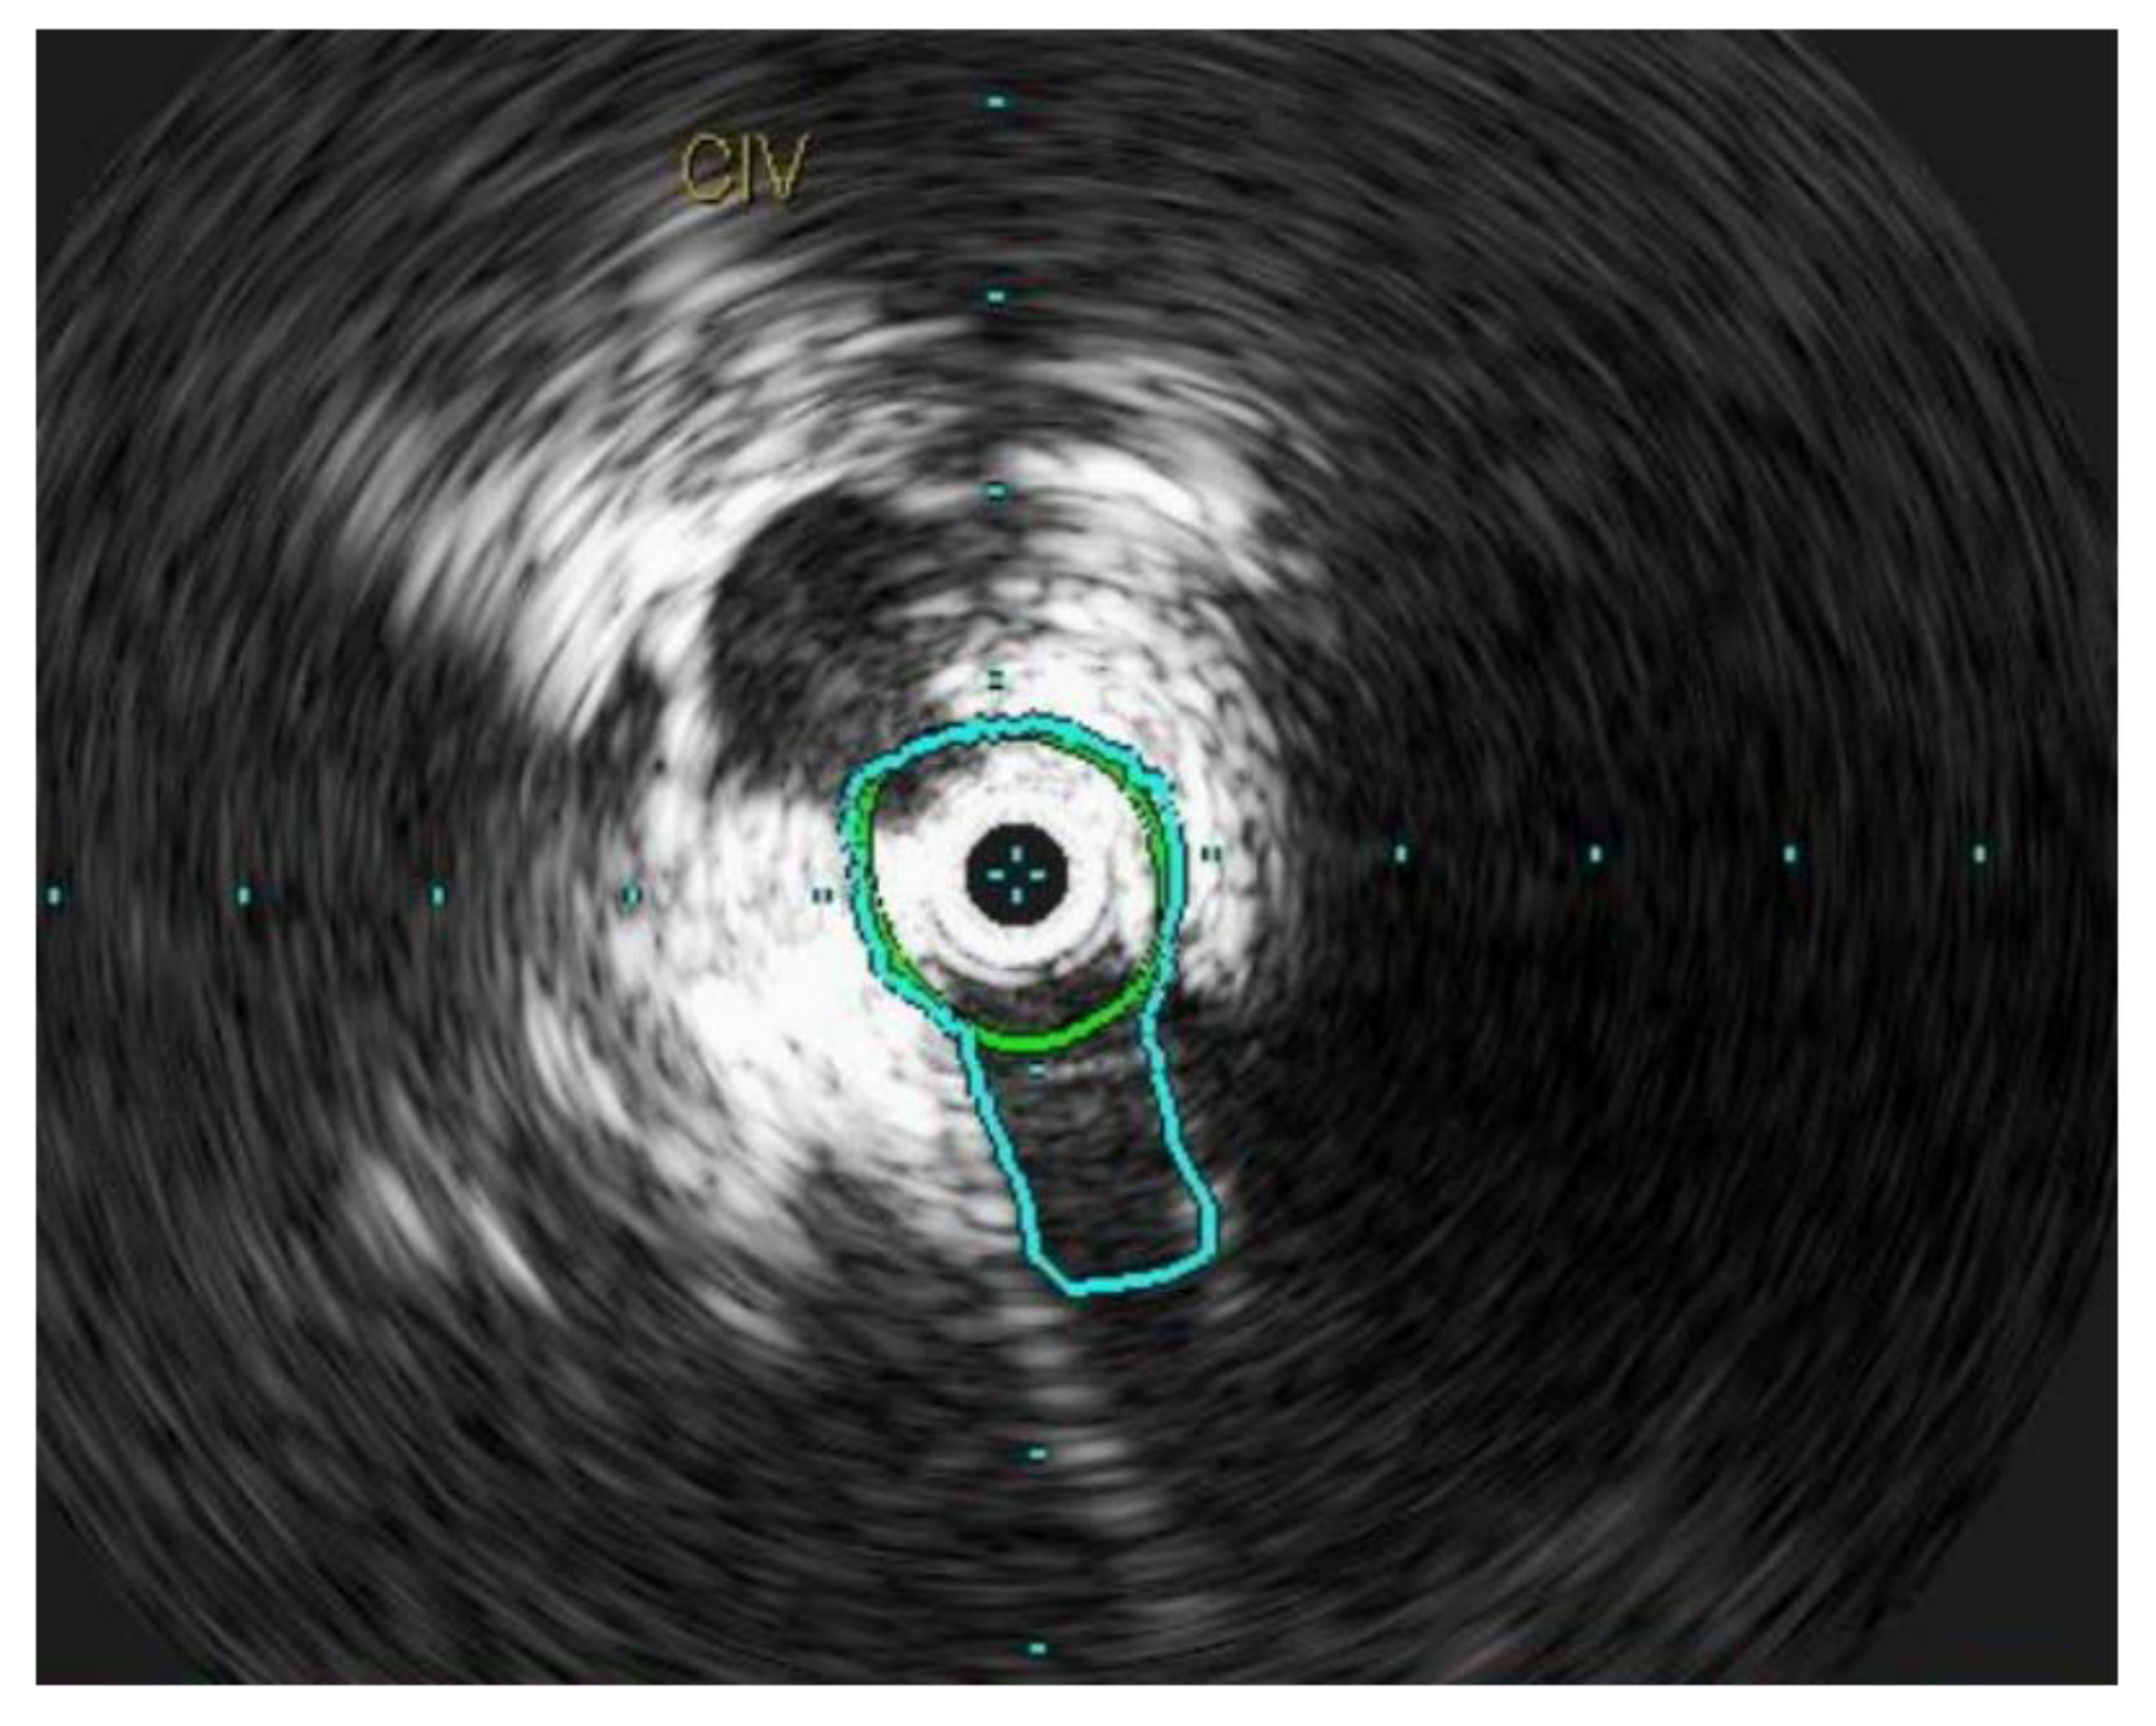

3.9. Intravascular Ultrasound

Intravascular ultrasound (IVUS) has made the art and science of treating CVD more precise, accurate, and personalized. It provides an allowance for the individualization of each patient’s treatment plan. Being the gold standard, IVUS provides high quality, real-time cross-sectional venous anatomy and is becoming increasingly available for venous interventions. Measurements obtained via IVUS provide guidance in iliofemoral venous stenting by providing ideal proximal and distal landing zones for the stents. In addition, IVUS provides crucial information for accurate stent sizing. Additionally, IVUS can be used in patients with advanced renal failure or severe allergy, to contrast. Through the use of IVUS, the following mishaps can be avoided: ‘jailing’ of the contralateral iliac vein orifice and ‘jailing’ of the ipsilateral profunda vein orifice [28,29].

Venography, even with multi-planar technique, can underestimate the presence and severity of iliac venous stenosis [30]. In one study, the median maximal area stenosis was noted to be significantly higher with IVUS than venography (69% vs. 52%, p < 0.0001). Iliac-caval confluence, a crucial technical landmark in venous stenting, correlated between venography and IVUS in only 15% of the patients. Therefore, sole reliance on venography can lead to undertreatment of venous lesions. Similarly, venography and IVUS correlated with each other in only 26% of cases as far as the distal landing zone for the stent was concerned [31].